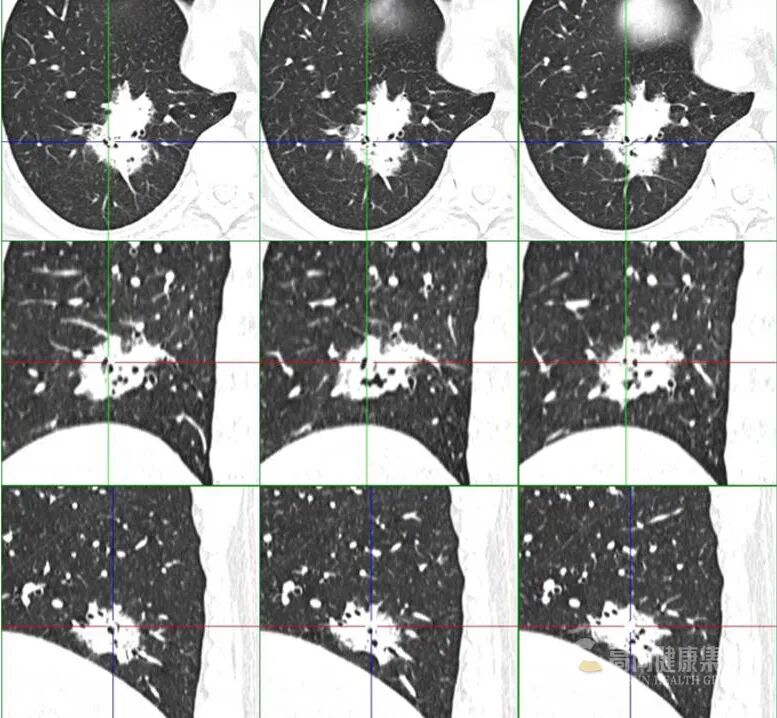

1、单一肺内病灶最主要是判断病变的性质,虽然比较像肿瘤,但仔细看病变内除了有支气管充气影,还有气泡影,病变局部边缘也有点模糊,因此这个炎症(脓肿)是有可能的,这个人肺泡灌洗出现克雷伯杆菌,结合病史那克雷伯肺炎(脓肿)是有可能的。

4、PPL 肿块型是有可能,内支气管扩张伴僵硬?

7、MALT 有可能,代谢上比较符合,病灶境界较清楚,周围还算干净,渗出不明显,支气管局部狭窄,患者无明显症状,就是 PPD 试验强阳不知怎么解释,不会是两者合并存在吧。

9、孤零零一个病灶,主要围绕气管生长,所示支气管基本通畅。有钙化,病灶整体密度偏高,病灶周围有少许磨玻璃,总体感觉偏向感染性病变,或者在已有病变 (如淀粉样变性什么的 (的基础上发生的感染,具体什么感染,结合临床,不象常见的,真菌放线菌等少见的要考虑下。

10、支气管迂曲扩张,考虑肺腺癌。

12、没有临床症状,单看影像,不看实验室检查结果的话,是比较像肺 MALT 的。

MALT 的支气管扩张并无支气管管壁的破坏。由于淋巴瘤组织浸润导致肺泡塌陷,支气管周围实质破坏造成的,这类支气管扩张在肿瘤治疗后有时可消失。

结节、肿块,边缘模糊

充气支气管粗大、扭曲

▼伴有空气支气管征充气的支气管粗大、扭曲;